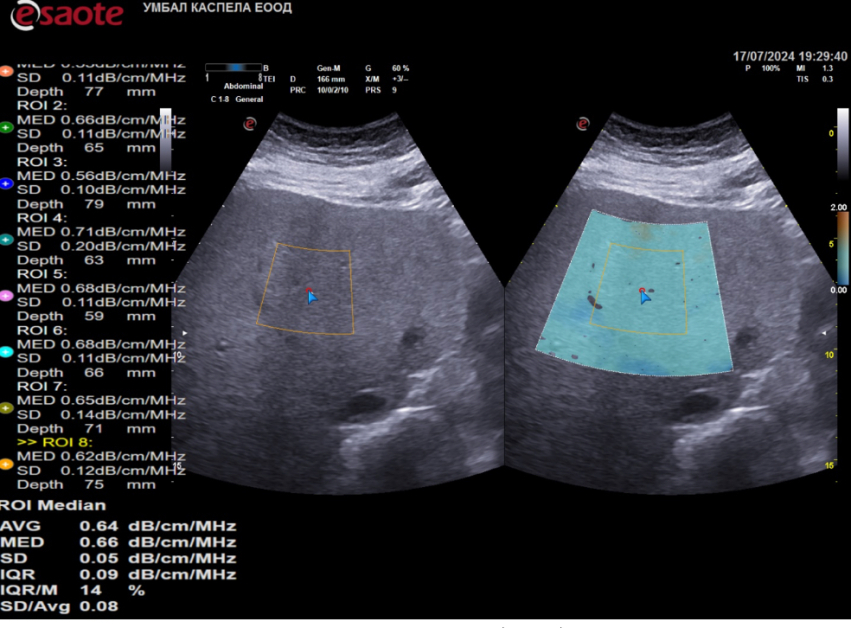

Клиниката по гастроентерология на УМБАЛ Каспела разполага с ехографски апарати от последно потомство на водещи производители- Hitachi Aloka, Philips, Esaote. Освен рутинната ехография те оферират и програмен продукт за качествена и количествена оценка на чернодробната стеатоза и фиброза- pSW и 2D еластография, QAI - количествена оценка на чернодробното омазняване.

Ехографското проучване посредством тези способи е бързо, безболезнено за пациента и без дискомфорт или лъчево натоварване.